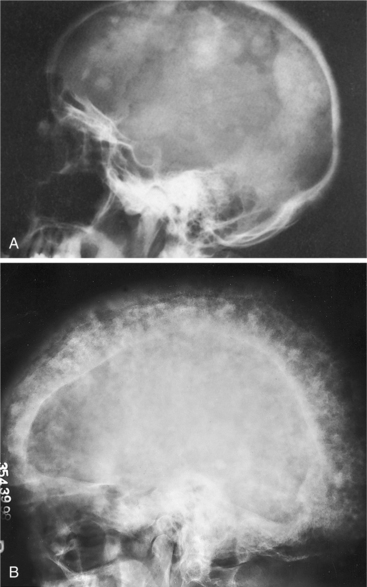

Typical neurologic deficits may include eighth cranial nerve involvement (most common) with hearing loss related to involvement of the ossicles or bony foraminal encroachment. Headaches may occur if the skull is involved, and the forehead may enlarge as the amount of bone in the skull expands and the foramen for the cranial nerves gets smaller (Fig. 24-11). Affected individuals also report tinnitus, vertigo, and hearing loss.

Figure 24-11 Clinical radiographs of the skull in later stages of Paget’s disease. A, Marked patchy sclerosis appears in the bone, the organized architecture is lost, and the bone becomes extremely thick, on occasion several times thicker than normal. B, Advanced involvement of the skull with marked thickening of the entire vault, areas of osteolysis, and patchy new bone formation resulting in a “cotton-wool” appearance called osteoporosis circumscripta cranii. This person experienced progressive hearing loss. (A from Bullough P: Orthopaedic pathology, ed 3, London, 1997, Mosby-Wolfe; B from Goldman L: Cecil textbook of medicine, ed 22, Philadelphia, 2004, WB Saunders.)